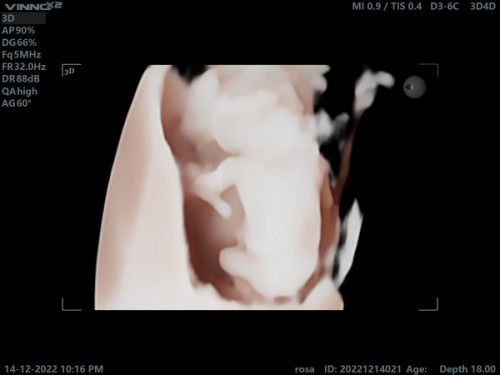

USG 16 minggu

Ada yg sama nggak bunda.. Waktu USG dedek nya kayak anakku ini.. Membelakangi cman kelihatan punggung nya.. Gtu itu knpa ya... Aku tdi tnya dokternya jawab nyaman normal" Aja.. . Ada yg tau informasi lebih lnjut nggak bunda... Bagi bagi informasi nya dong bunda